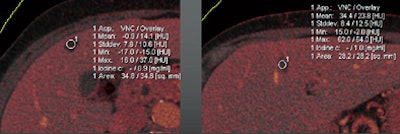

| Images are of a 65-year-old male patient who underwent a single acquisition at dual-source CTC. Above, a stenosing carcinoma was seen in the proximal sigmoid colon in 3D endoluminal views (left, middle) and 2D view (right). Below, an 18-mm colorectal adenoma was also found in the proximal sigmoid colon, and also appears to be enhancing. Bottom image shows an enhancing liver metastasis in the same patient. Virtual unenhanced (grayscale) images are created by electronically subtracting the contrast media. All images courtesy of Dr. Anno Graser. |

The technique can be used to determine the contrast media uptake of the polyp, as well as the baseline density of the lesion, directly measuring enhancement in HU and measuring the iodine in the lesion in grams per mL.

The mean enhancement of adenomas was 55 ± 27 HU.

The mean enhancement of hyperplastic lesions was 13 ± 10 HU.